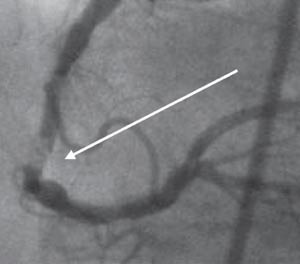

Når sirkulerende blod eksponeres for subendotelialt vev, aktiveres både blodplatene og koagulasjonssystemet og fører til danning av en plate-fibrin-plugg (trombe) på skadestedet (18) (fig 1, 2). Koagulasjonsaktiveringen finner sted på fosfolipidoverflaten til aktiverte blodplater. Samtidig er koagulasjonsproduktet trombin en viktig plateaktivator, slik at de to hemostatiske systemene henger nøye sammen. Trombin spalter fibrinogen til fibrin, og fibrinmolekylene kan binde seg til hverandre og danne et nettverk. Dette nettverket forsterkes ved påvirkning av koagulasjonsfaktor XIII, som også aktiveres av trombin (19, 20). Således har trombin en helt sentral rolle ved danningen av plate-fibrin-pluggen.

Aterosklerotiske lesjoner inneholder bestanddeler, også vevsfaktor, som medfører at både blodplater og koagulasjonssystem aktiveres umiddelbart hvis det tilkommer en plakkruptur eller plakkerosjon (21). Undersøkelser har sannsynliggjort at plakkrupturer kan forekomme langt hyppigere enn kliniske hendelser skulle tilsi hos individer med aterosklerotisk hjertesykdom (22). Dette forklares ved at plate-fibrin-pluggen ofte er av begrenset størrelse og ikke fører til okklusjon av arterien (19). Ved hjelp av kroppens fibrinolytiske system kan tromben løse seg opp spontant og rupturen etter hvert tilheles.